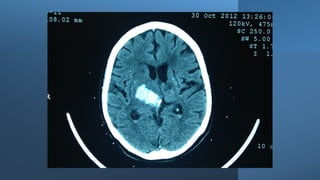

Hemiparesis with facial weakness: brain CT scan or brain MRI, with or

NB: Urgent non-contrast brain CT scan is the most suitable imaging

Paresis, where? Hemiparesis withfacial weakness: brain CT scan or brain MRI, with or without contrast. Hemiparesis without facial weakness: Brain/upper cervical MRI, with or without contrast. NB: Urgent non-contrast brain CT scan is the most suitable imaging modality in patients with acute hemiparesis because of its availability in Emergency Departments (usually), and it is rapid (the period of the test is very brief (compared to MRI). Drawback: poor visualization of posterior fossa structures because of boney artifacts, except in posterior fossa hemorrhages. Paraparesis: dorsal spine MRI, with or without contrast or in some cases, brain/cervical MRI (with or without contrast).